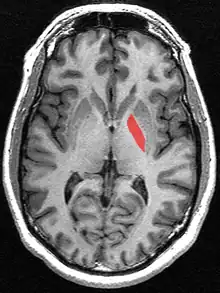

Globus pallidus (in red) shown within the brain | |